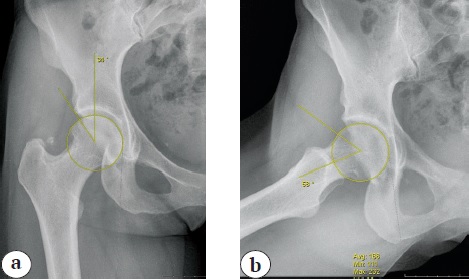

В связи с сохранением болевого синдрома пациентка обратилась в нашу клинику. При клиническом обследовании провоцирующие FADIR (Flexion Adduction Internal Rotation) и FABER (Flexion Abduction External Rotation) тесты были отрицательными при классической методике их проведения, и лишь при максимальном сгибании бедра вызывали у пациентки болевые ощущения, в отличие от теста HEER (Hyper Extension External Rotation), сопровождающегося болью уже при малых углах переразгибания бедра. После проведения дополнительных лучевых методов обследования (КТ и МРТ) были выявлены минимальные анатомические особенности, характерные для ФАИ синдрома: угол a — 58°, угол Виберга — 34°, индекс ретроверсии — 0,12.

Рис. 1. Предоперационные рентгенограммы с расчетом: a — угла Виберга; b — угла α

Figure 1. Preoperative X-rays with the measurements of: a — Wiberg’s angle; b — α angle